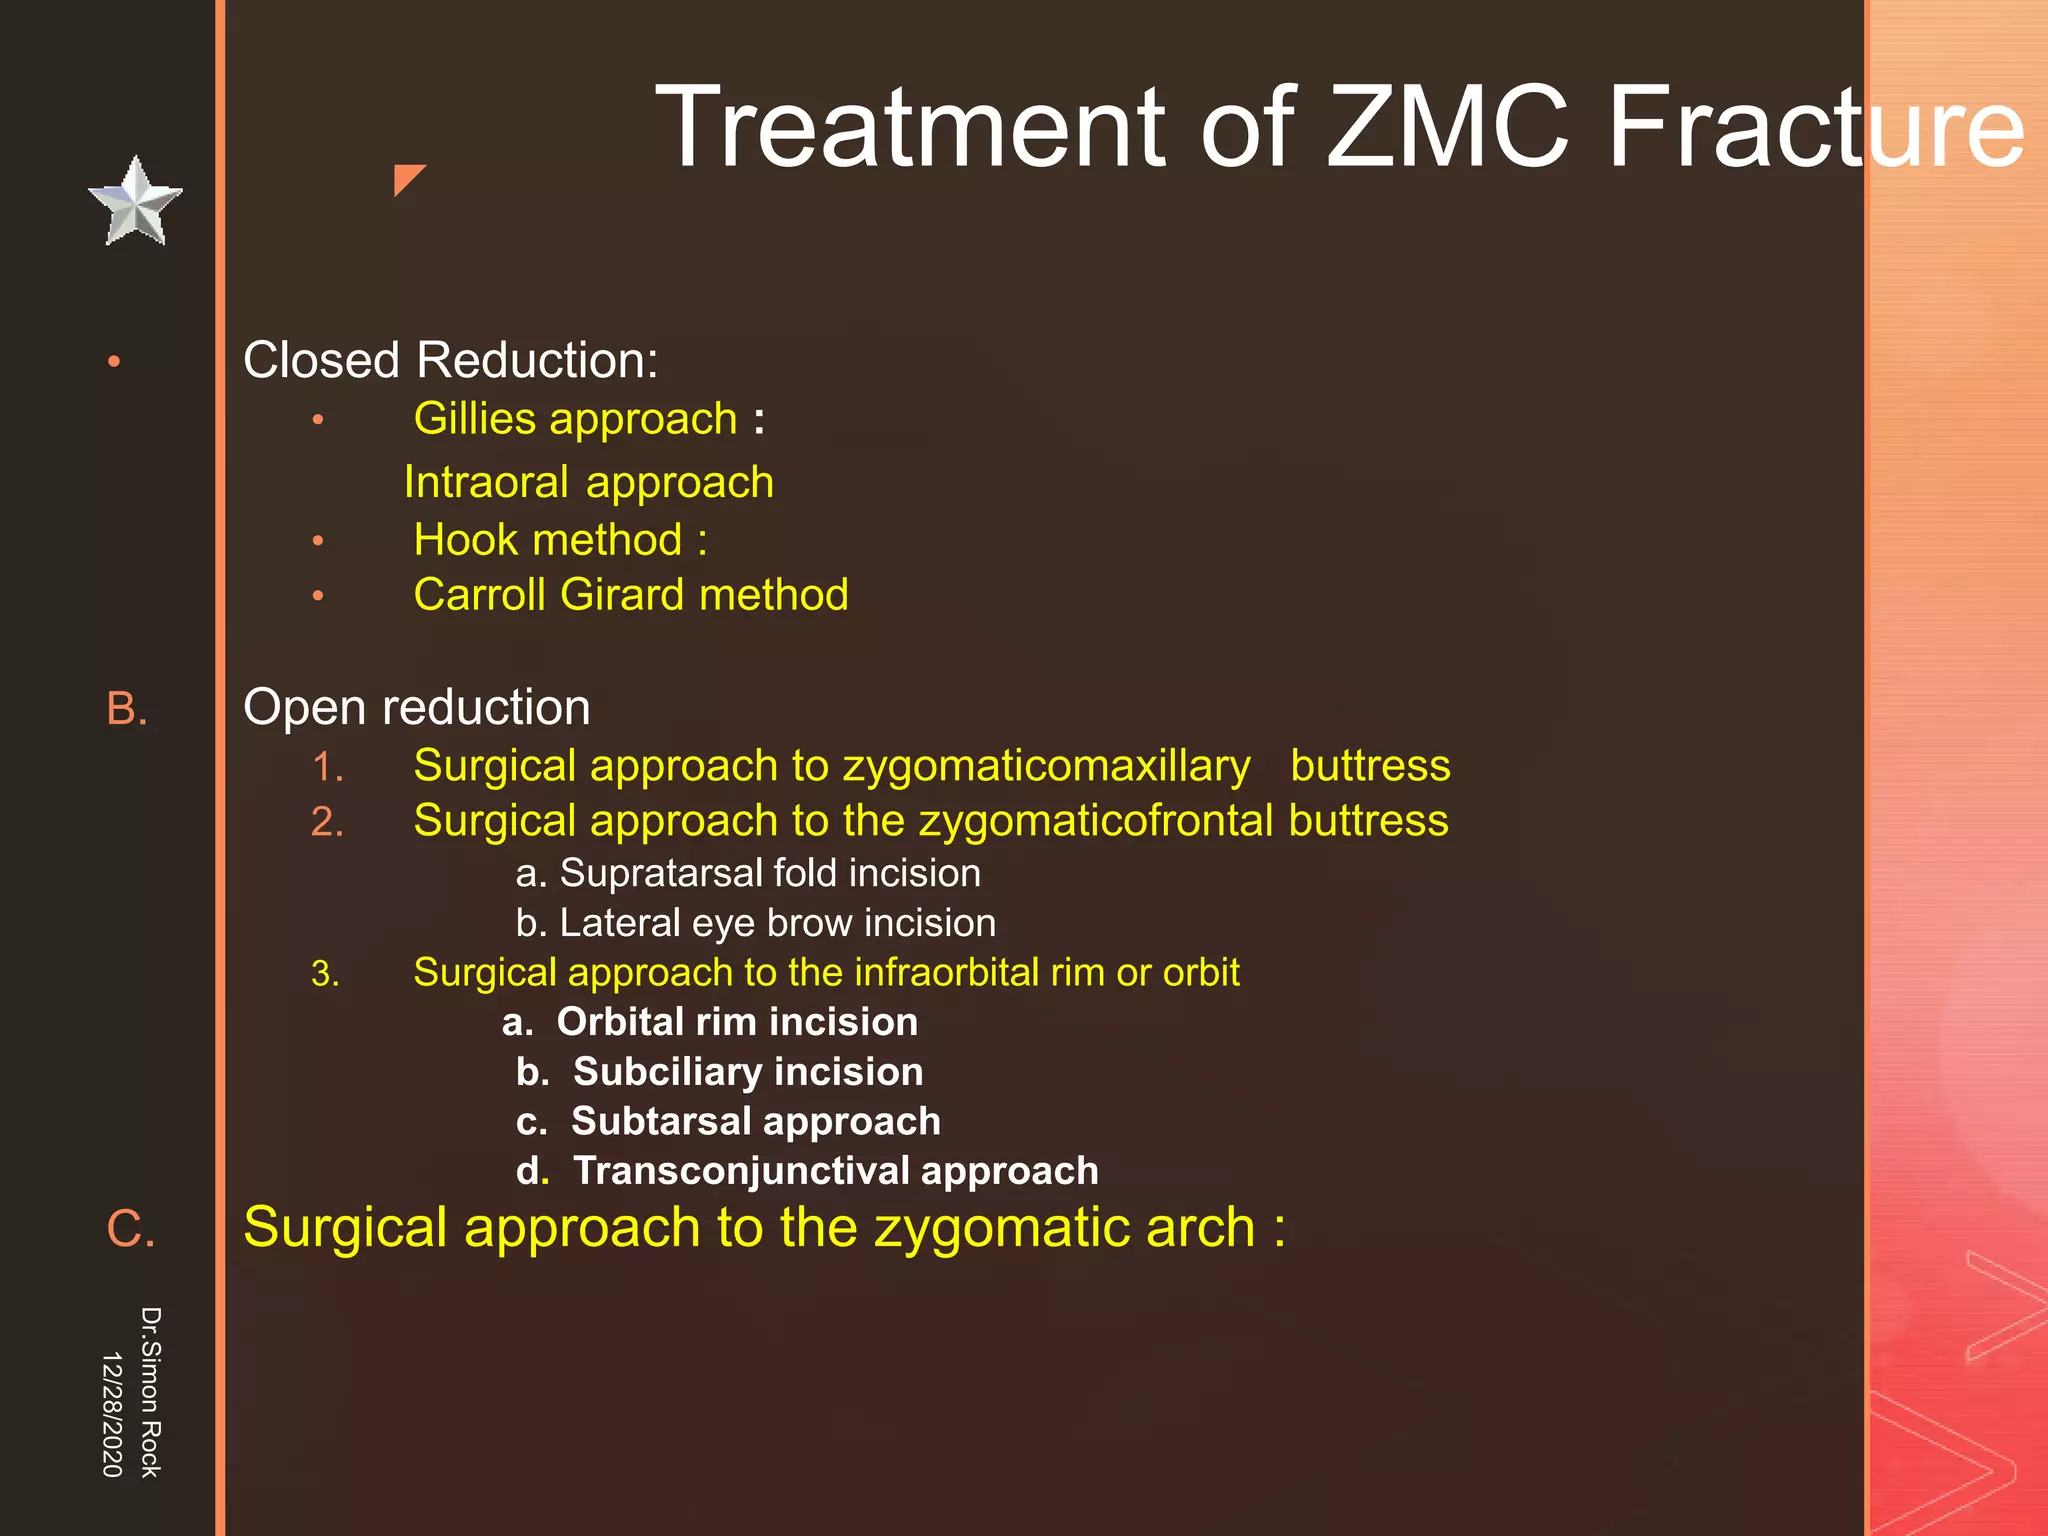

This document discusses the anatomy and fractures of the zygomatic bone. It notes that the zygoma forms the cheekbone and articulates with several other facial bones. Zygomatic fractures most commonly occur in the arch or body due to blunt trauma. Diagnosis involves checking for diplopia, ecchymosis, and other signs of orbital or facial bone involvement. Treatment may involve closed or open reduction based on the severity of displacement. Closed reduction techniques try to elevate the bone back into position without surgery, while open reduction requires surgical exposure and fixation of the fracture site.